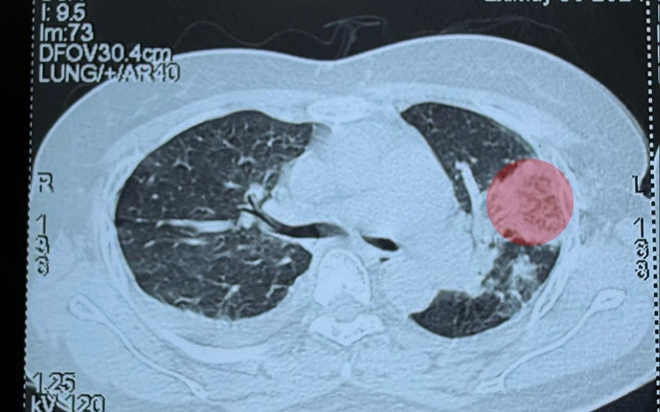

Kết quả chụp cắt lớp phổi cho thấy các đám đông đặc rải rác, có nhiều ổ áp xe ở trong phổi. Kết quả cấy máu cho thấy có vi khuẩn tụ cầu vàng kháng Meticillin (tụ cầu kháng thuốc). Sau thời gian điều trị tại khoa Cấp cứu, sức khỏe của bệnh nhân đã dần ổn định, bệnh nhân không cần thở oxy và đã giảm sốt.